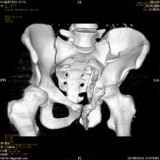

Уважаемые коллеги! Хотелось бы услышать совет по тактике лечения представлленого больного.Поступил после лечения в одном изотделений области. Травма 2,5 месяца назад. После выведенияиз шока был произведен остеосинтез перелома бедра, предплечья, до перевода к нам проводилосьвытяжение по оси шейки бедра за стержень, введенный в большой вертел. На сегодня деформацияригидна, клинически мобильности не определяется. Заранее признателен. P.S. Данный вид травм не включен в перечень "высокотехнологичных операций", направить длялечения по квотам Минздрава очень сложно.

Все-таки надо бы начать не с КТ, а с обзорного снимка таза и косых проекций впадины.

Это обзорные и косые снимки

Привет, Леонид. Оскольчатый высокий двухколонный перелом в такие сроки трогать не надо, т.к. это про такие переломы сказано: "кто с ножом на Ж. пойдет тот в ней и останется...".